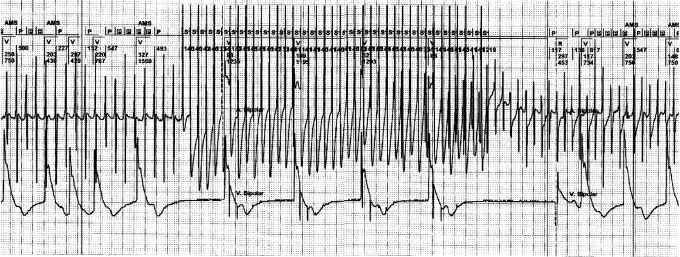

Figure 1 .

Regular atrial tachycardia with a 2:1 lock in. This is a continuous strip from the pacemaker memory. The upper canal of each strip shows the interpretation of the pacemaker of the atrial and ventricular rhythm. The lower canal shows the intracardiac atrial rhythm, derived from the atrial electrode. It is clearly visible that in the beginning of this regular atrial tachycardia, every second atrial depolarisation remains undetected by the pacemaker. This is caused by the programmed postventricular atrial blanking (PVAB). This PVAB (100 msec) was programmed for the prevention of far field R-wave sensing. A slight irregularity of the atrial rhythm in the beginning of the second strip, makes the atrial tachycardia out of the PVAB period and allows the pacemaker to detect all atrial activity. This allows the pacemaker to engage a mode switch to DDI. It is only at this moment that the regular atrial tachycardia can be detected and the window for the implementation of pace interruption is opened. P=sensed atrial activity, P in black box=sensed atrial activity in the refractory period, V=paced ventricular event, R=sensed atrial event. AMS=automatic mode switch.

Failing to detect bouts of atrial tachycardia by a PM results from the postventricular blanking period (PVAB), which is programmed to prevent far field R-wave (FFRW) sensing in the atrial channel. This blanking or ‘closure’ interval of the atrial channel in DDD PM rules out sensing immediately after a ventricular event and can cause the ‘2:1-lock in phenomenon’, where every second atrial depolarisation of the atrial tachycardia is blanked (figure 1).4 This failure to detect every second atrial activation can be avoided by maximal shortening of the blanking interval. The selected time, however, should be counterbalanced towards FFRW sensing in the atrial channel. FFRW sensing, and normal P-wave sensing, will introduce double counting. This double counting has to be avoided as atrial pace intervention protocols can have undesired side effects such as the induction of AF in this situation. An option to prevent FFRW sensing includes the shortened tip-to-ring distance of the atrial electrode.5 Digital signal processing replacing the current analogue signal analysis is also advocated to prevent FFRW sensing but this method is still in its infancy.6 We assume that this novel processing is unnecessary when the FFRW amplitude can be reduced to <0.2 to 0.1 mV by electrode configuration.